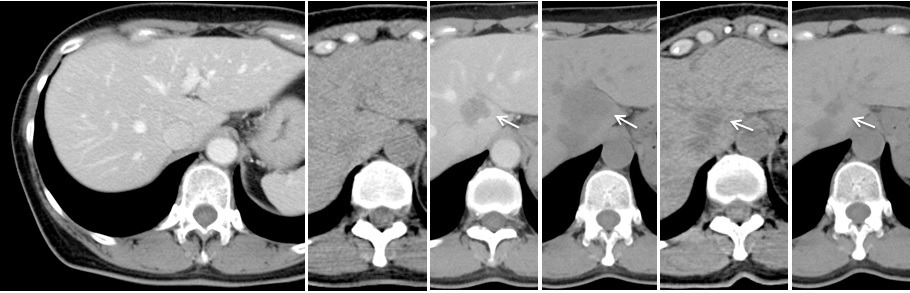

ただし、この論文にはない、上図の「治った!!」という時点の画像を、さらに特殊なSPECTによる検査で確認した画像が下図です。骨転移巣が完全に消失したままであることが確認されています。2018年1月で、骨転移巣が臨床的完全奏効(cCR)となってから、満5年に達します。

この図は、論文(Kuranishi F, et al. Int J Breast Cancer, 2018;article ID 4879406, 11 pages.)の中のFig. 2として公開されています。